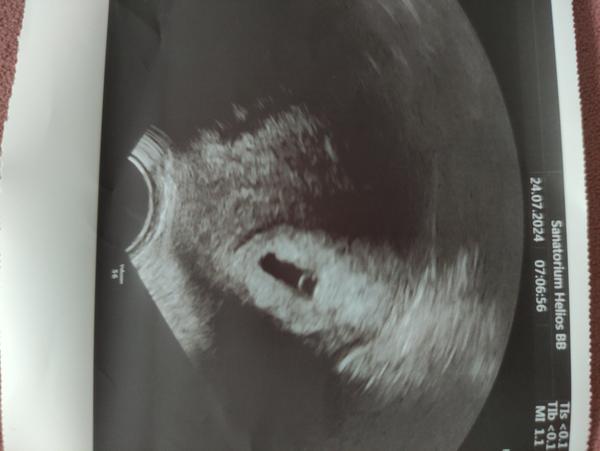

@nikadominikanika ved v niektorych car robia uz na 14dpt sona, aha toto pridavala jedba kocka do skupiny velmi pekne

Ako sa dobre pozerajú tieto obrázky 😍 prajem vám všetko iba to dobre 🍀 nech to ide len dobrým smerom ❤️

@anika02 super 🙂🙂je to na dobrej ceste